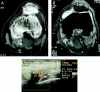

Results: Crystallographic analyses showed monosodium urate (MSU) crystals in the specimens of the four patients; hydroxyapatite and calcium pyrophosphate dihydrate (CPPD) crystals were not found. A diffuse soft tissue thickening was seen on plain radiographs but no calcifications or ossifications of the tophi. CT disclosed lesions containing round and oval opacities, with a mean density of about 160 Hounsfield units (HU). With MRI, lesions were of low to intermediate signal intensity on T(1) and T(2) weighting. After contrast injection in two cases, enhancement of the tophus was seen in one. Colour Doppler US showed the tophi to be hypoechogenic with peripheral increase of the blood flow in three cases.

Conclusion: The MR and colour Doppler US images showed the tophi as masses surrounded by a hypervascular area, which cannot be considered as specific for gout. But on CT images, masses of about 160 HU density were clearly seen, which correspond to MSU crystal deposits.